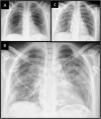

Negative Pressure Pulmonary Edema Due to Severe Bronchospasm